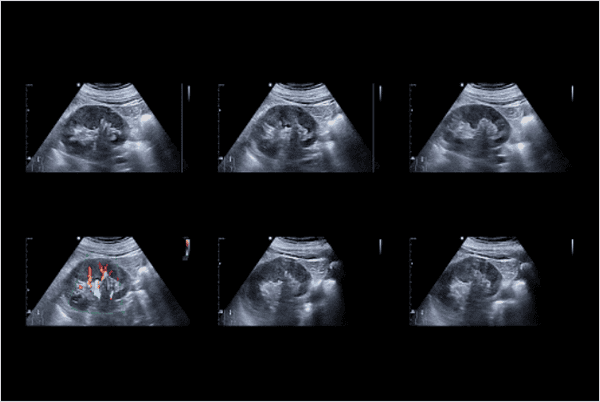

영상 진단

초음파, CT, MRI 등을 이용하여 신장의 크기, 모양, 위치를 확인하거나 이상 소견(종양, 낭종 등)을 찾습니다.